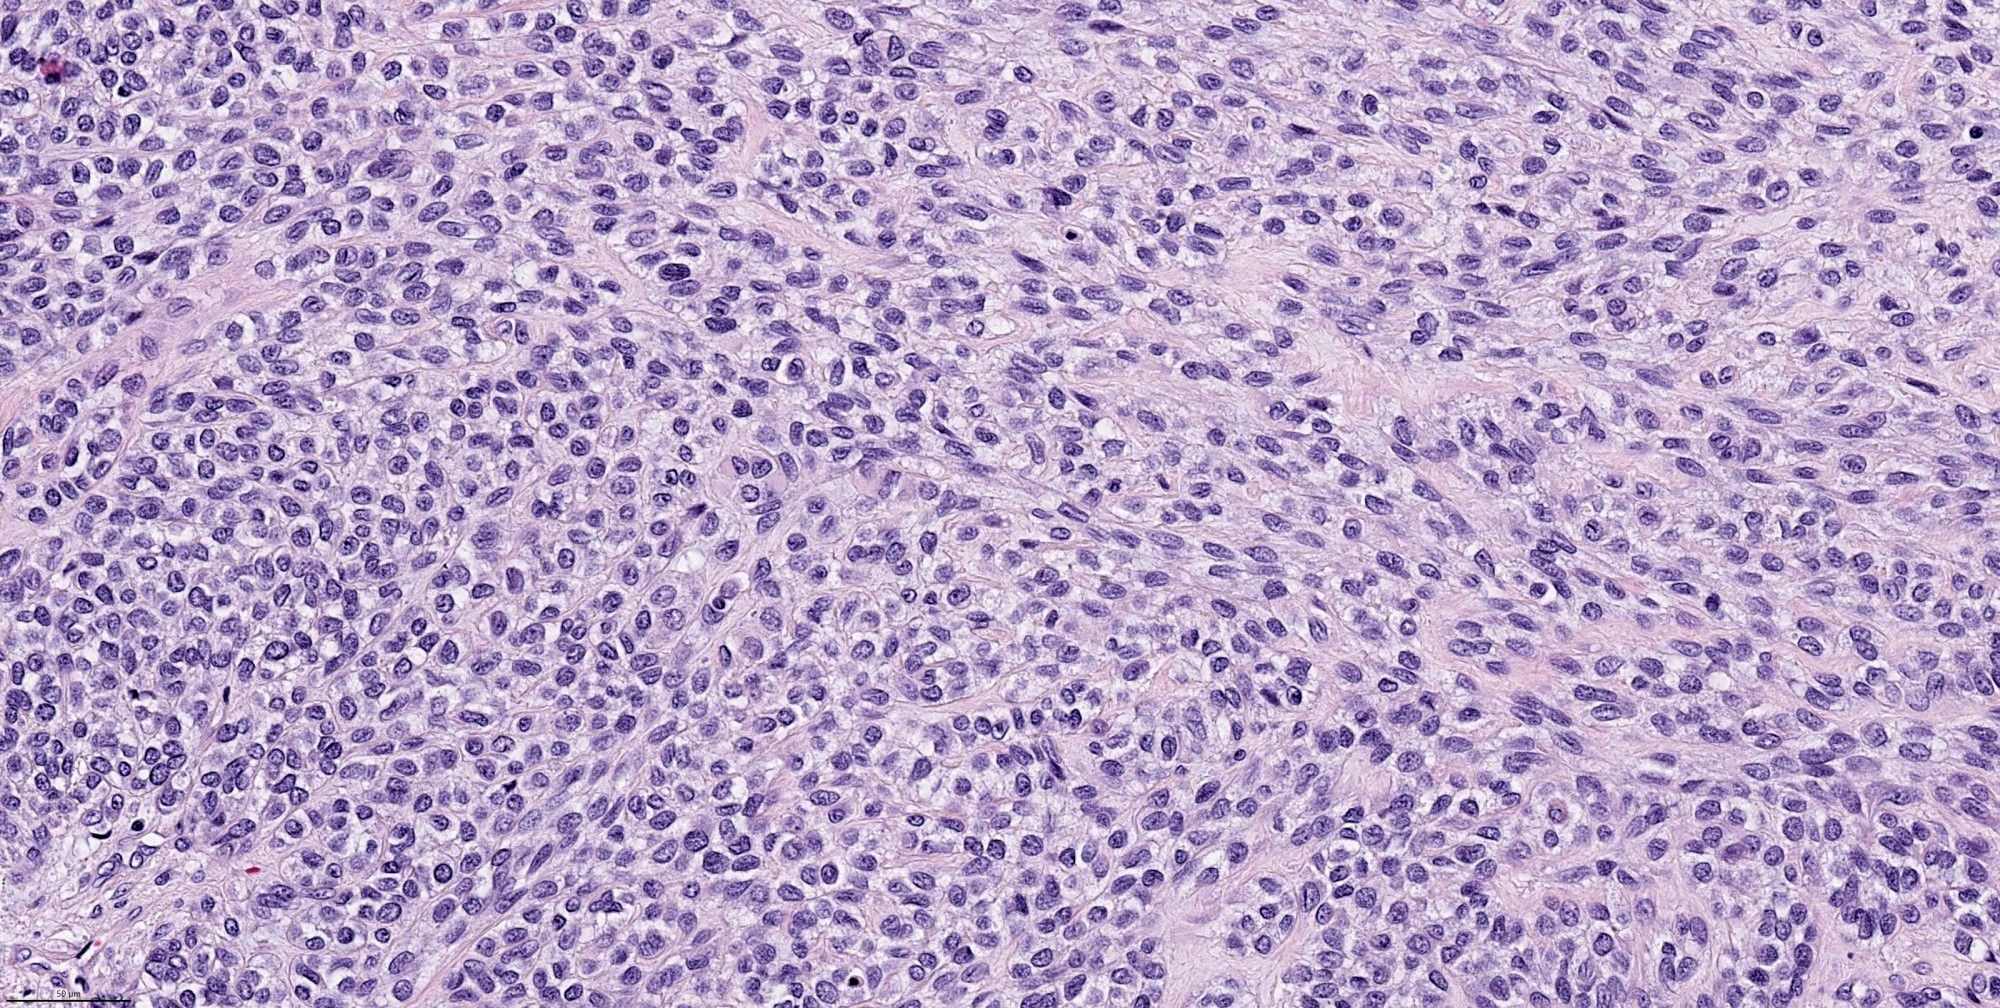

- Composed (near) entirely of myoepithelial cells showing various cytologic features, including clear cell, epithelioid, plasmacytoid or spindle cell morphology

- Common architectural patterns include solid, trabeculae, cords, nests and single cells

Contributed by Abeer Salama, M.D. and Bin Xu, M.D., Ph.D.